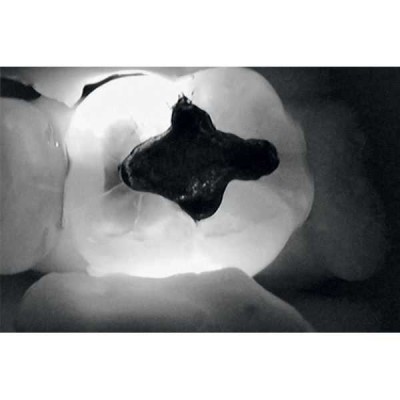

Весь секрет заключается в технологии DIFOTI за счет генерируемого прибором трансилюминационного (трансиллюминация - яркое сквозное освещение) лазерного излучения в нерентгеновском диапазоне волн. Если объяснять это простым языком, то это излучение, занимающее диапазон между видимым светом и рентгеновским диапазоном, которое проходит сквозь твердые ткани зуба, при этом области, не пропускающие свет (например, области кариозного поражения) отображаются в виде затемненных на общем фоне участков.

Рентгенограммы и снимки, полученные с помощью KaVo DIAGNOcam, относятся к методам диагностики, прекрасно дополняющим друг друга. С помощью рентгенологической диагностики Вы в дальнейшем сможете беспрепятственно проверить и дополнить данные KaVo DIAGNOcam, исключив часть рентгеновского излучения для пациента. На снимках отчетливо визуализируются структуры коронковой части зуба, располагающиеся выше уровня десневого края. Таким образом, становится возможным раннее распознавание кариеса и проведение профилактического, малоинвазивного лечения. Ваши пациенты будут в восторге!

- Полная диагностика наддесневых поверхностей зуба и вторичного кариеса.

- Обнаружение кариеса на раннем этапе развития.